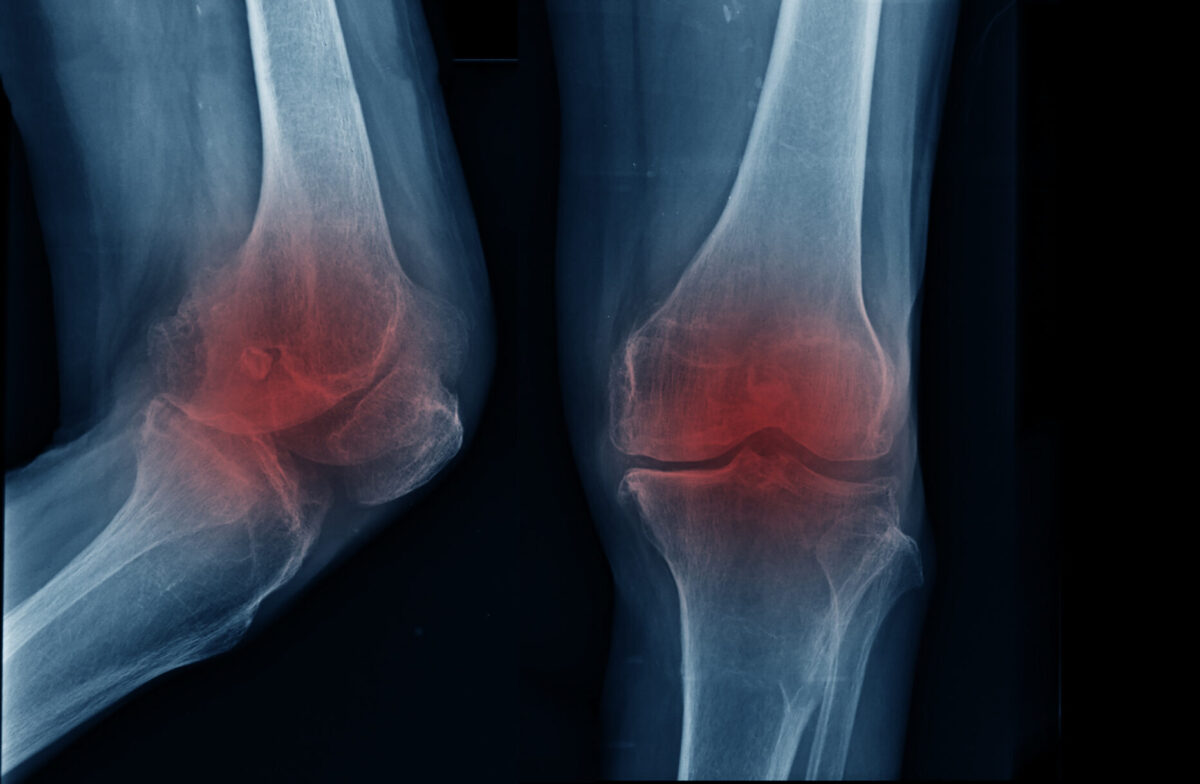

「膝が痛くて階段の上り下りがつらい」「買い物に出かけたいけれど、歩くのが不安」──そんな悩みを抱える方は少なくありません。特に変形性膝関節症は年齢とともに増える代表的な関節疾患で、習志野市にお住まいの方からも多くご相談をいただきます。

変形性膝関節症の痛み緩和に効果的な方法とは?

結論から言うと、膝にかかる負担を減らし、血流や筋肉の柔軟性を改善するケアが痛み緩和のカギになります。